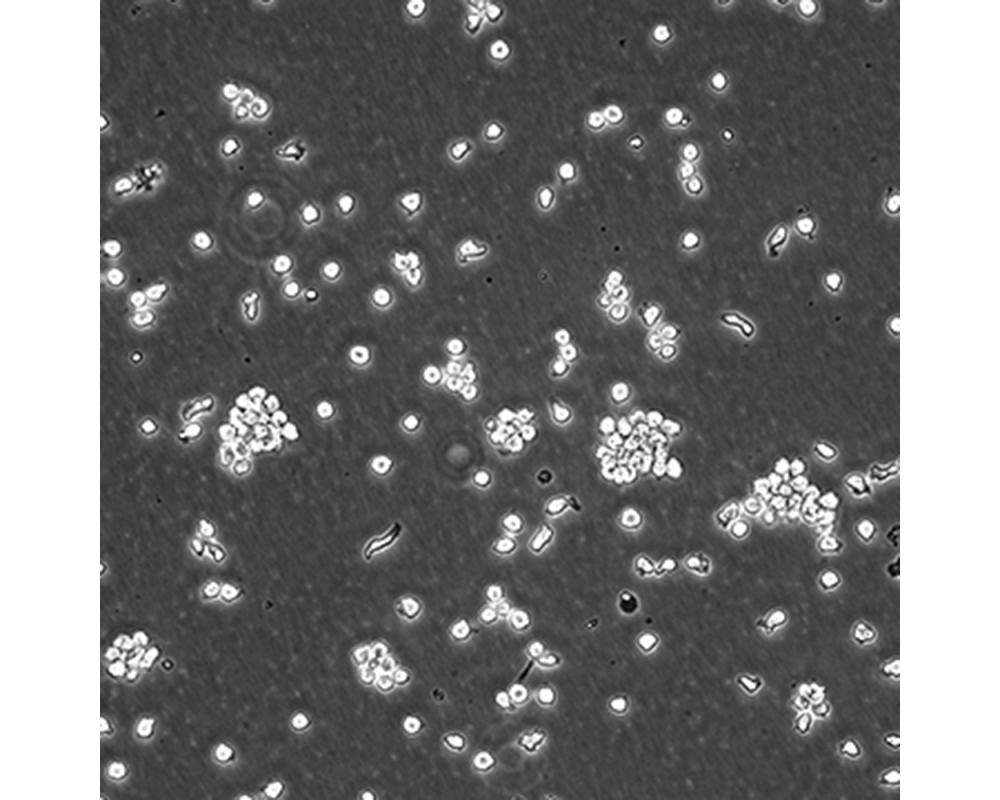

產品名稱 SUP-T1

中文名稱 人T淋巴細胞瘤細胞

組織來源 T淋巴瘤細胞;男性

生長特性 懸浮

培養(yǎng)基 1640,90%;FBS,10%;雙抗。

傳代方法 Maintain cultures at a cell concentraion between between 1 X 10(5) and 1 X 10(6) viable cells/ml.

培養(yǎng)條件 Atmosphere: Air, 95%; CO2, 5%。Temperature: 37℃